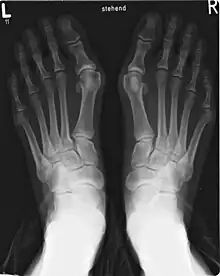

Hallux valgus

Um joanete é uma deformidade da Articulação metatarsofalângica que liga o dedo grande do pé. O dedo grande do pé, muitas vezes, se dobra em direção a outros dedos e a junta se torna vermelha e dolorosa. O início é gradual e as complicações podem incluir bursite ou artrite.[1]

A causa exata não é clara.[2] Os fatores propostos incluem o uso de sapatos excessivamente apertados, o histórico familiar e a artrite reumatóide. O diagnóstico baseia-se geralmente nos sintomas, com o apoio de raios-X. No caso do dedo mínimo, há uma situação semelhante, designada como bunionette.[1]